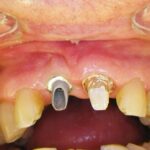

Este paciente llegó al consultorio con reabsorción dentinaria (pérdida de la estructura del diente). Por ello se le extrajo el diente, se le colocó un implante y se restauraron las piezas con coronas de cerámica pura.